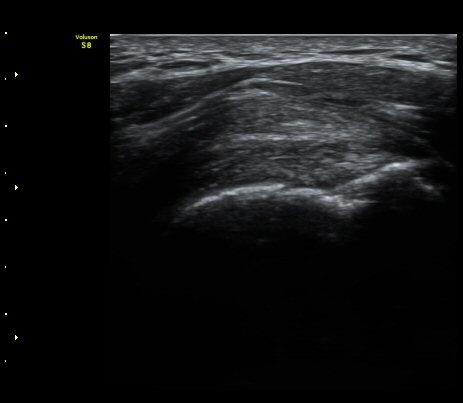

±Ø»ó°ÇȾ´Ü¸é°Ë»ç¿¡¼­ ±Ø»ó°ÇÀÇ ±¤¹üÀ§ÆÄ¿­ ¼Ò°ßÀ» º¸ÀÓ(»çÁø 4)